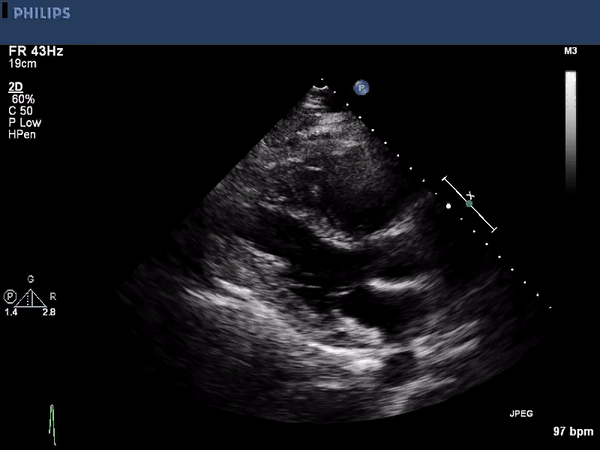

The echocardiographic images above show a large right ventricular

thrombus. The first image is a parasternal long axis view highlighting

the right ventricular inflow tract. A mobile thrombus is seen near the

anterior border. The other two images are using an apical approach

showing the right and left ventricle. Again a mobile the thrombus is

seen within the right ventricle. Contrast is used to enhance the

thrombus borders.